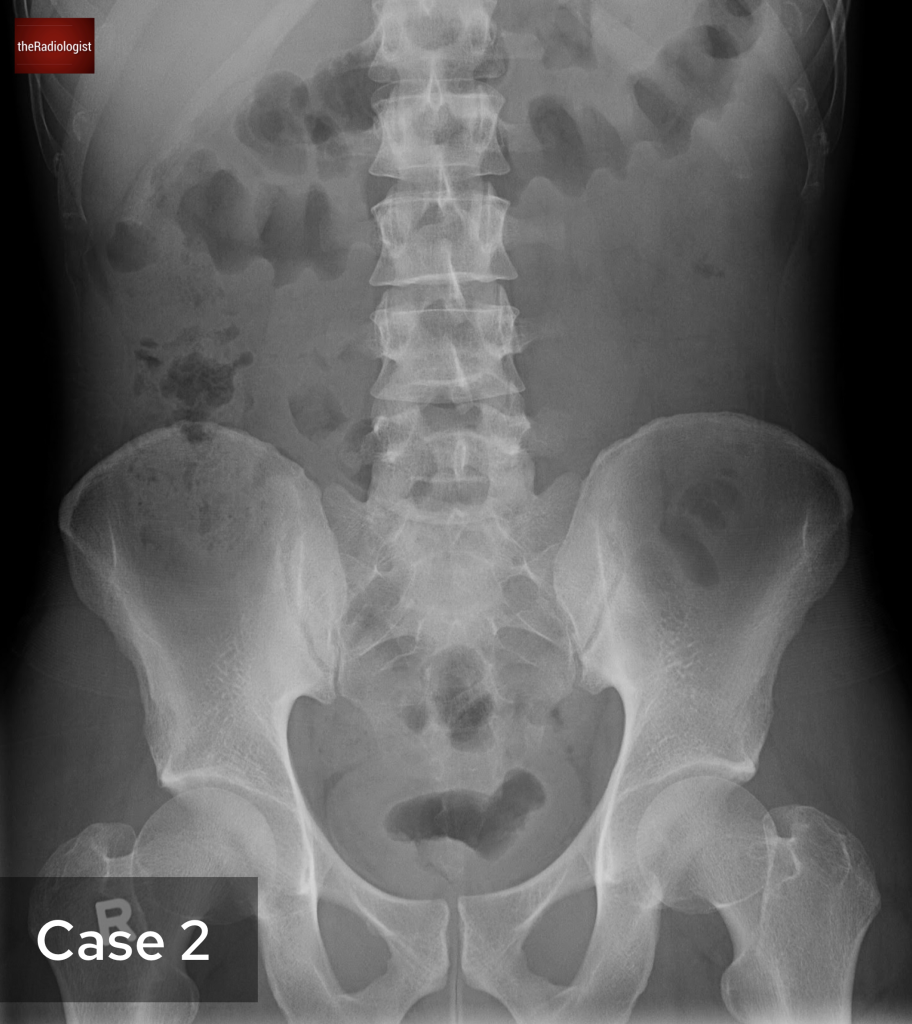

Although we couldn’t see this on our CT case, irregularity of the endplates can be seen after a few weeks on X-Ray and CT as well as loss of disc space. MRI is more sensitive and we are looking for high T2 or STIR signal within the endplates, disc and paraspinal tissues and psoas muscles. Gadolinium contrast can help as we may see enhancement of the endplates, disc and peripheral enhancement of any abscesses. It’s important on MRI to ensure there is no significant central canal stenosis secondary to abscess formation or vertebral collapse.